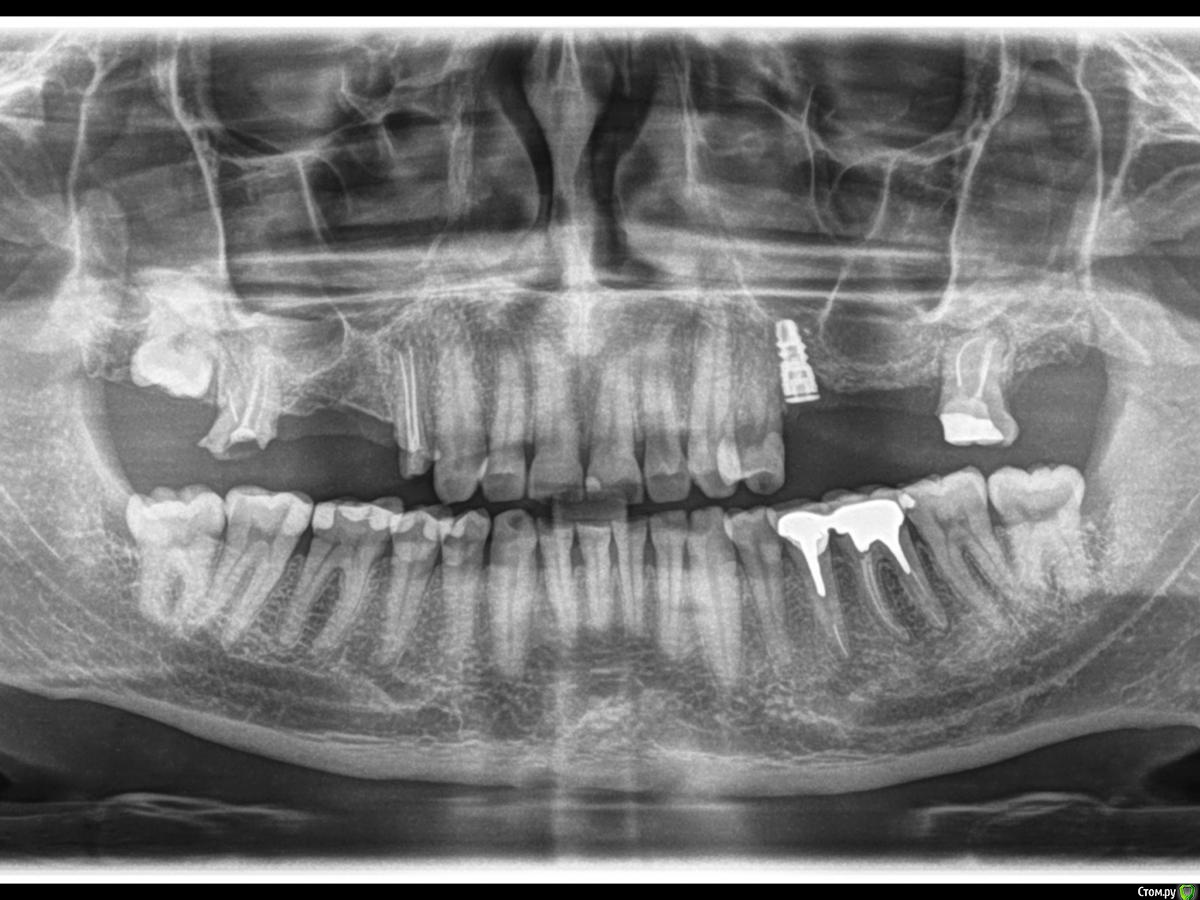

Самарец Опубликовано 12 февраля, 2018 Поделиться Опубликовано 12 февраля, 2018 (изменено) Доброго дня! Опорная 5—ка моста умерла.... Имплантолог имеющий большой авторитет в этой области в нашем городе озвучил план поставить мост на имплант 5—ку и зуб 8—ку. Кость за время ношения моста на зубах ушла и не вернулась... А синуслифтинг я ужасно боюсь делать...Вкрутили немецкий имплант Schutz Impla 9мм на 4.5мм. Вошли в пазуху на 1 мм. Через год поставил формирователь. Сейчас уже надо продолжать идти по плану врача, но я в сомнениях и затягиваю время, т.к. предполагаю что это не совсем правильное решение и в скором времени что—то или зуб или имплант вывалится.... Имплант жестко закреплён в кости, а зуб имеет подвижность (начитался инета и сам технарь). Доктор же настаивает на том, что все будет гуд..... Вопрос к профи возможен ли положительный исход при таком плане протезирования? Заранее благодарю! Изменено 12 февраля, 2018 пользователем Самарец Ссылка на комментарий

red_butler Опубликовано 12 февраля, 2018 Поделиться Опубликовано 12 февраля, 2018 Зуб мудрости удалить, и поставить еще один имплант в позицию 2.7 1 Ссылка на комментарий

Doc Опубликовано 13 февраля, 2018 Поделиться Опубликовано 13 февраля, 2018 Категорически не рекомендуется объединять свой зуб и имплант. И уж тем более в мосте с пролетом такой длины. Они обязательно подерутся и кто-нибудь один выиграет. 2 Ссылка на комментарий

Самарец Опубликовано 16 февраля, 2018 Автор Поделиться Опубликовано 16 февраля, 2018 (изменено) Спасибо господа за консультации и советы! Сегодня пообщался с врачом. Будем устанавливать имплант рядом с 8—кой на место 7—ки. Врач говорит 8—ку не будем трогать. А я вот придерживаюсь мнения что от неё надо избавляться, т.к. На КТ видны гранулемы на верхушках корней.... Потом будут наверное проблемы.... Изменено 16 февраля, 2018 пользователем Самарец Ссылка на комментарий

red_butler Опубликовано 16 февраля, 2018 Поделиться Опубликовано 16 февраля, 2018 Я бы восьмой удалил, если оставлять, то перелечивать и протезировать 1 Ссылка на комментарий